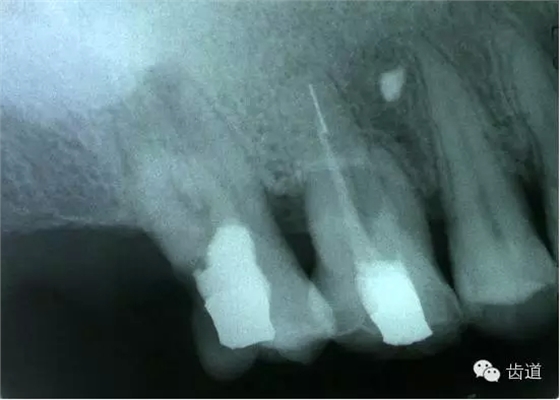

2.檢查:探診疼痛,且有鮮血;用根管長(zhǎng)度測(cè)量?jī)x探測(cè)可疑穿孔處,儀器發(fā)出報(bào)警聲;插診斷絲到可疑穿孔處拍X線片,可見診斷絲已超出髓腔范圍。

左上7近中頰根器械折斷

右上6腭根器械折斷